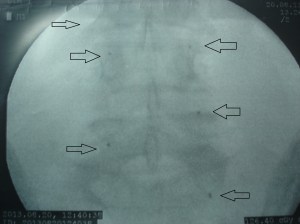

Las imágenes a continuación pertenecen a un caso con una remisión sintomática casi completa y un grado muy alto de satisfacción de la paciente tratada.

En las imágenes de RX y RMN se observan los cambios degenerativos (señalados en rojo las articulaciones interapofisarias artrósicas), también la presencia de múltiples hemangiomas, y las imágenes intraoperatorias de control de los implantes de oro (con flechas).